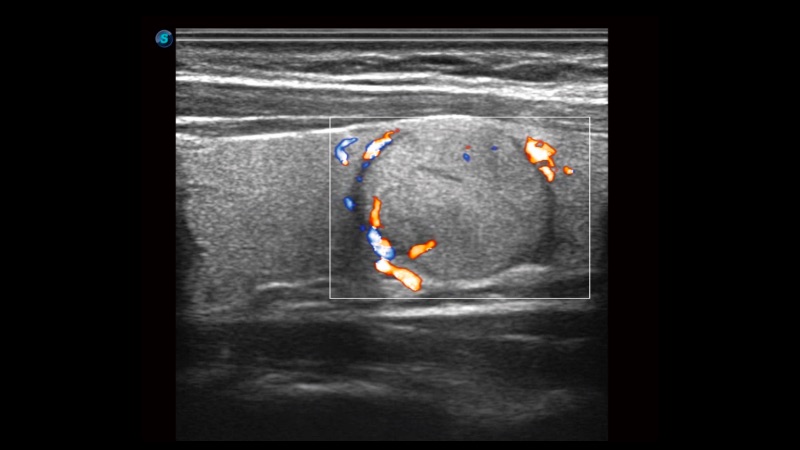

高分辨率血流成像技術(shù)提高了對(duì)低速血流信號(hào)的檢測(cè)能力。在提高空間分辨率的同時(shí),也克服了血流外溢現(xiàn)象,為用戶(hù)提供更加真實(shí)的血流動(dòng)力學(xué)信息。